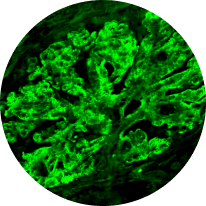

Immunofluorescence

Distinguishes between C3G and primary IC-MPGN, detecting glomerular deposition of C3 through staining of C3 fragments and/or Ig2,6,21

C3 deposits

(C3G)

C3/Ig deposits

(IC-MPGN)

C3G vs primary IC-MPGN under immunofluorescence

Histological analyses uncover disease activity and kidney damage in C3G and primary IC-MPGN. Under immunofluorescence, C3 staining intensity indicates the level of deposition of C3 breakdown products, providing diagnostic confirmation of C3G.2,23

Histological evidence from patients with repeat biopsies has shown that immunofluorescent staining patterns may change over time and sometimes lead to a switch from a diagnosis of primary IC-MPGN to C3G, or vice versa.23,24

C3G

C3G is defined by dominant glomerular C3 staining (≥2 orders of magnitude [OOM] compared with other immune reactants, including Ig).2-6

Primary IC-MPGN

IC-MPGN exhibits Ig-dominant or codominant C3 deposition under immunofluorescent staining.4,6

Microscopic images: Courtesy of Patrick D. Walker, MD, Senior Renal Pathologist at Arkana Laboratories.